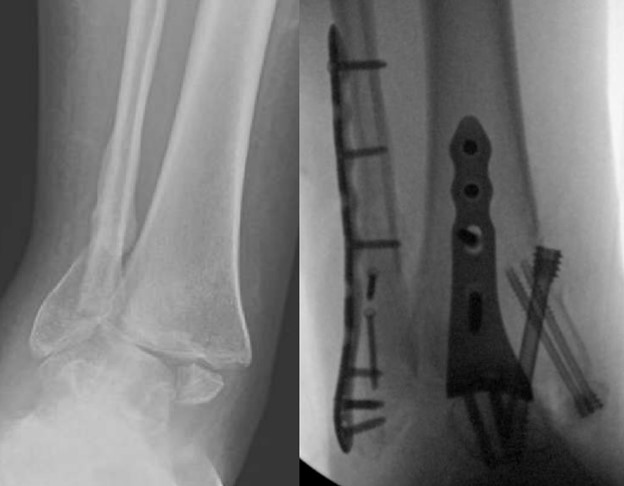

Led by Dr. Vinod Panchbhavi, a world-renowned orthopaedic foot and ankle surgeon, our fellowship covers all aspects of foot and ankle surgery including trauma, reconstruction, ligament and tendon injuries, arthroscopy, arthroplasty, and midfoot and

education. While he practices all aspects of foot and ankle surgery, he has made especially significant contributions in advancing our understanding of charcot arthropathy and Lisfranc injuries.

where he performed around 100 cases of total ankle arthroplasty. His other clinical interests include minimally invasive surgery and foot and ankle trauma.